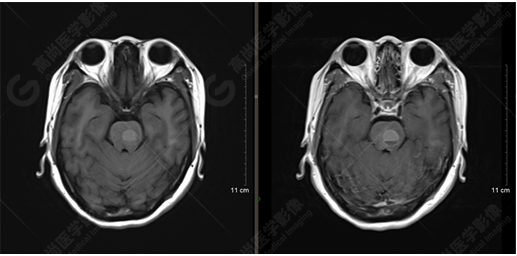

T1WI及T1增強(qiáng)序列

影像表現(xiàn):橋腦見一類圓形異常信號(hào)影,直徑約1.3cm,呈T1WI稍高信號(hào),T2WI及FLAIR序列高信號(hào),其內(nèi)見高低信號(hào)分層,增強(qiáng)后無明顯強(qiáng)化。大腦鐮前部旁見兩個(gè)結(jié)節(jié)影,較大者直徑約1.4cm,呈各序列等信號(hào),增強(qiáng)后呈均勻明顯強(qiáng)化,鄰近大腦鐮增厚、強(qiáng)化。右側(cè)額葉腦白質(zhì)內(nèi)見一斑點(diǎn)狀等T1長(zhǎng)T2信號(hào)影,F(xiàn)LAIR序列呈高信號(hào),增強(qiáng)后無強(qiáng)化;余腦實(shí)質(zhì)內(nèi)未見局灶性信號(hào)異常,增強(qiáng)后未見異常強(qiáng)化。各腦室、腦池大小、形態(tài)均正常,中線結(jié)構(gòu)居中,幕下小腦無異常。矢狀面示垂體大小形態(tài)正常,未見局灶性信號(hào)異常。